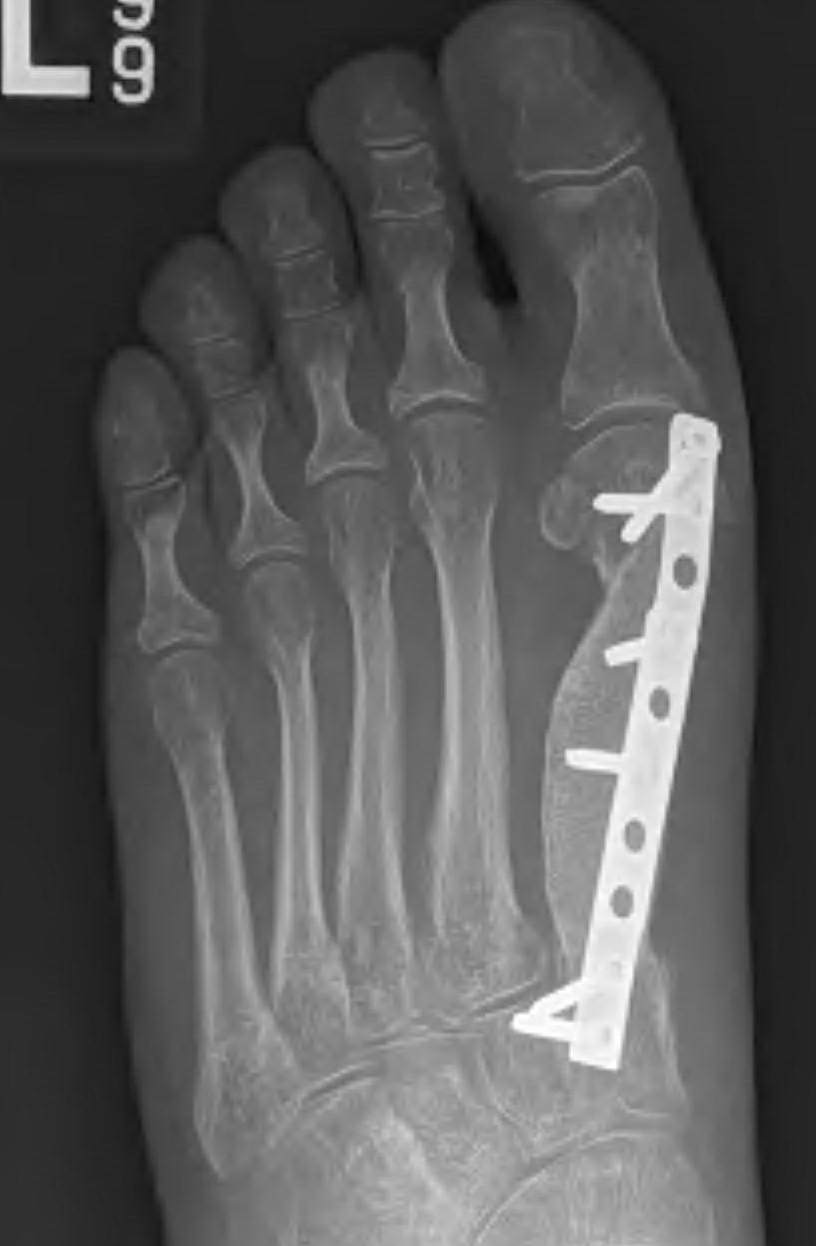

Aneurysmal bone Cyst

Metatarsal metaphysis most common site, followed by calcaneum

Treat with curettage and BG

Can excise an expendable bone like the metatarsal